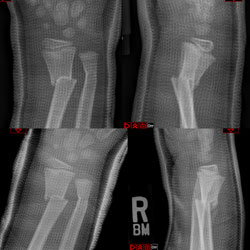

"Satisfaction of Search" Never Stop Looking -- Before and After Surgery

Current Concept Review

Daniel Y. Hong, Stephanie N. Moore-Lotridge, John J. Block, Hernan Correa, Jennifer L. Halpern, Ginger E. Holt, Christopher Stutz, Jeffrey E. Martus, Tim Schrader, Jonathan G. Schoenecker